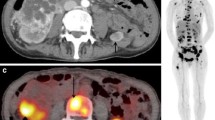

A 66-year-old male patient with bladder cancer (cT3N1) developed lymph node metastasis and bone metastasis after neoadjuvant chemotherapy and radical cystectomy. (a) The maximum intensity projection (MIP) of FDG-PET shows two regions of abnormal FDG uptake in the pelvis. (b) CT of FDG-PET/CT and (c) PET/CT showed moderate FDG uptake (SUVmax, 7.2) corresponding to a 1.5-cm enlarged para-aortic lymph node (arrow), suggesting lymph node recurrence. The little FDG uptake on the left side of the lymph node recurrence lesion is a physiological excretion in the left ureter. CT of FDG-PET/CT and (e) PET/CT showed strong FDG uptake (SUVmax, 13.0) corresponding to a mild sclerosis of the left pubic symphysis (arrow), suggesting bone metastasis. It is difficult to detect this bone metastasis only by (d) CT